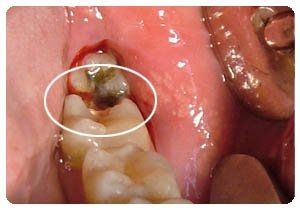

二个是病理性的:患有口腔疾病,如:龋齿、牙龈炎、牙周炎等这些口腔问题也会导致磨牙的,这种情况就要针对性的去看医生的。小孩子睡觉磨牙是怎么回事?>>点击在线咨询详情<<